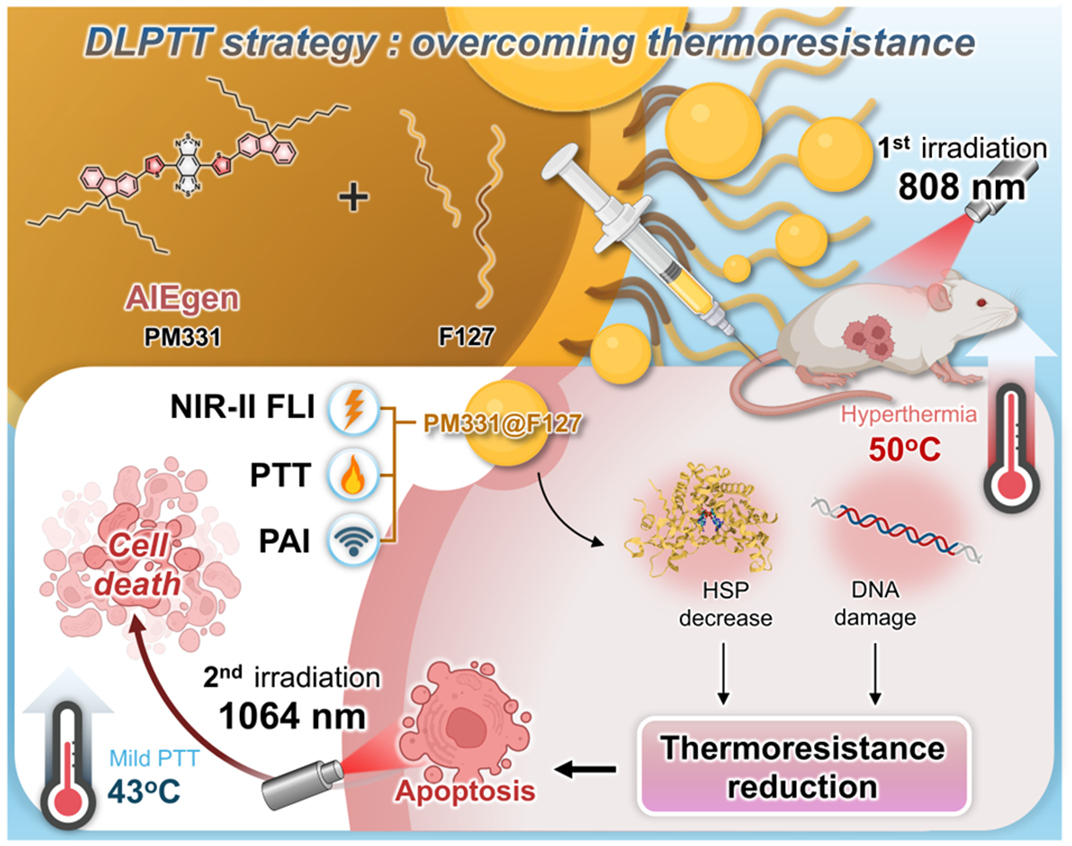

Jun 11, 2025Dual-Laser Strategy Revolutionizes Breast Cancer Photothermal TherapyResearchers developed a dual-laser photothermal therapy (DLPTT) strategy for breast cancer therapy, which enhances tumor ablation while minimizing damage to surrounding healthy tissues by using nea... Breast cancer is the most prevalent malignancy among women worldwide. Phototheranostics—an approach that uses light both to detect and treat cancerous lesions—has drawn growing attention due to i...